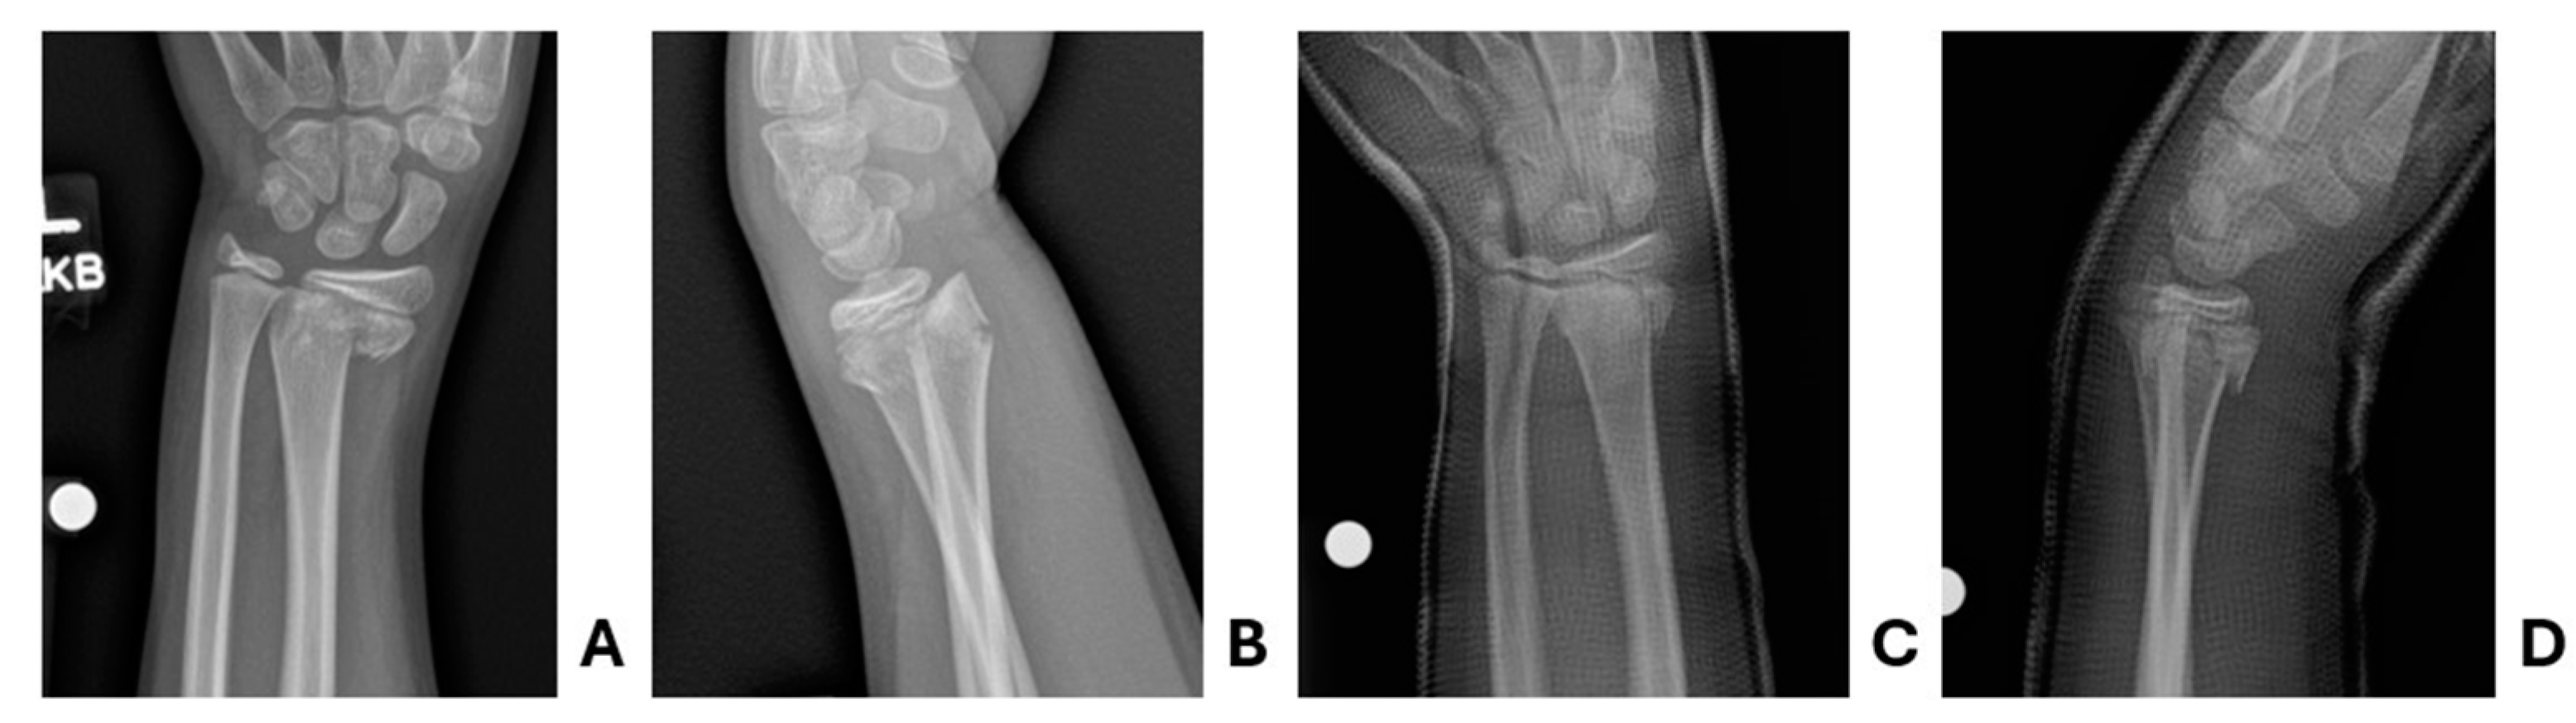

Figure 4. Patient one pre- and post-reduction radiographs. Pre-reduction A anteroposterior and B lateral radiographs demonstrating acute Salter-Harris Type II distal radius fracture. One-week post-reduction C anteroposterior and D lateral radiographs demonstrating stable interval reduction.

In the ED, the patient was found to have an obvious deformity with accompanying tenderness and mild swelling of the left wrist. He was neurovascularly intact distally. It was a closed injury without violation of the skin. Full trauma assessment was performed given the mechanism of injury and notable for a small forehead hematoma indicating head trauma. X-rays of the left wrist, radius, and ulna were obtained. Given a normal neurologic examination, no signs of a basilar skull fracture, and no altered mental status, computed tomography of the head was deferred. X-ray imaging was subsequently notable for an acute, displaced, mildly angulated fracture of the distal left radial metaphysis with extension into the physis, Salter-Harris type II (Figure 4).

Orthopedics was consulted, recommending reduction and immobilization with cast placement. Given the severe mechanism of injury, close observation and serial neurological examinations were favored over advanced imaging of the head. To facilitate the need for close observation and orthopedic reduction, the decision was made to perform supraclavicular nerve block over procedural sedation. This was preferred as the team wished to closely observe Glasgow Coma Scale, while not delaying care of his distal radius fracture. Ultimately, supraclavicular block was performed without complications. He was provided an additional 50 mcg of fentanyl for analgesia during the closed reduction, which was performed successfully on the first attempt. Biplanar fluoroscopy and post-reduction x-rays confirmed appropriate reduction before the patient was placed in a bivalved, long-arm, fiberglass cast. There were no procedural complications. Following an appropriate observation for his head injury, he was discharged with plans to follow-up with Orthopedics in one week for repeat radiographs. X-rays obtained during follow-up 1, 2, and 3 weeks later demonstrated stable alignment of the fracture site.